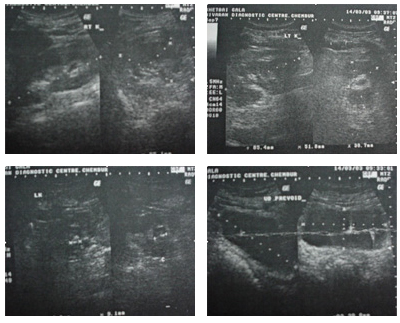

A 58-year-old lady had history of chronic left loin pain associated with repeated episodes of urinary tract infection. Ultrasonography showed ill-defined hypoechoic mass extending from renal pelvis to the upper ureter. IVU showed a filling defect extending from inferior group of calyces upto the upper ureter on the left side. CT scan confirmed a soft tissue lesion within the lumen of the left pelvis and upper ureter with an irregular hyperdense area seen within. Cystoscopy with left sided RGP confirmed a huge filling defect in the upper ureter and the pelvis. Diagnostic ureterorenoscopy was performed and a smooth globular large whitish tumour was seen extending from the upper ureter at L-3 and extending into the pelvis. Ureteroscopic biopsies showed evidence of normal mucosa with no suspicion of malignancy. A left sub-costal incision was used to expose the left upper ureter and pelvis grossly bulging tumour was felt from the outside. A U-shaped uretero-pyelotomy was performed and the entire lesion extending from the upper ureter to the lower calyx was delivered out of the incision. There were three vascular fronds attached to the mucosa, which were separately diathermised. Frozen section of the tumour showed no evidence of malignancy, the mass was suspected to be a benign fibroepithelial polyp. The lady had an uneventful post-operative stay and was home in 5 days. Her DJ stent was removed after 3 weeks. Histopathology confirmed a giant fibroepithelial polyp.